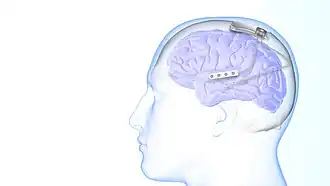

The use of neurostimulation to treat epileptic seizures is only recommended in those who have failed multiple medications for the treatment of their seizures. The NeuroPace RNS system was approved for use by the FDA in 2013 and is the only medical device for epilepsy that uses responsive neurostimulation.[1] The device is surgically implanted into the patient's head with electrical leads placed near the site in the brain that is believed to be the origin of the patient's seizures. These leads record electrical activity in the brain and deliver electrical stimulation when a seizure is detected.[9] The device keeps a record of abnormal electrical activity that is reviewed by a neurologist to improve the detection and treatment of seizures. The patient is able to record when they are having symptoms with the device to see if their symptoms are correlating with seizures.[1] The use of responsive stimulation has found to be effective for seizure reduction. Some patients are able to achieve complete seizure freedom with responsive and non-responsive neurostimulation.[10]